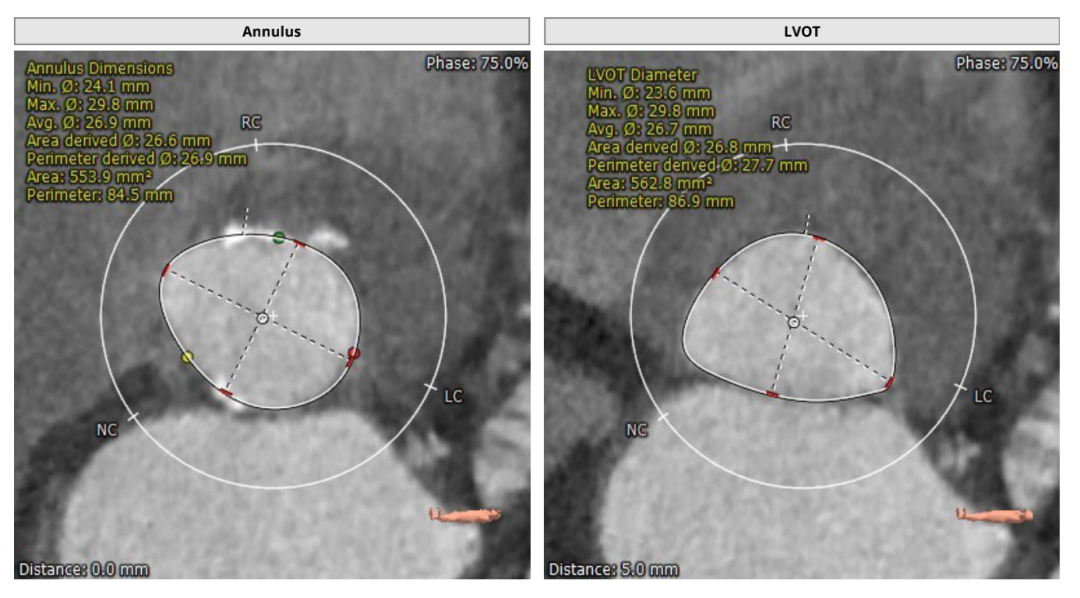

主动脉根部解剖结构

瓣环直径:26.9mm,左室流出道直径:27.7mm

主动脉窦:36.2*37.5*36.8mm,STJ:31.4mm

左冠高度:13.0mm,右冠高度:19.4mm

升主动脉直径:38.3mm,心脏夹角:48度